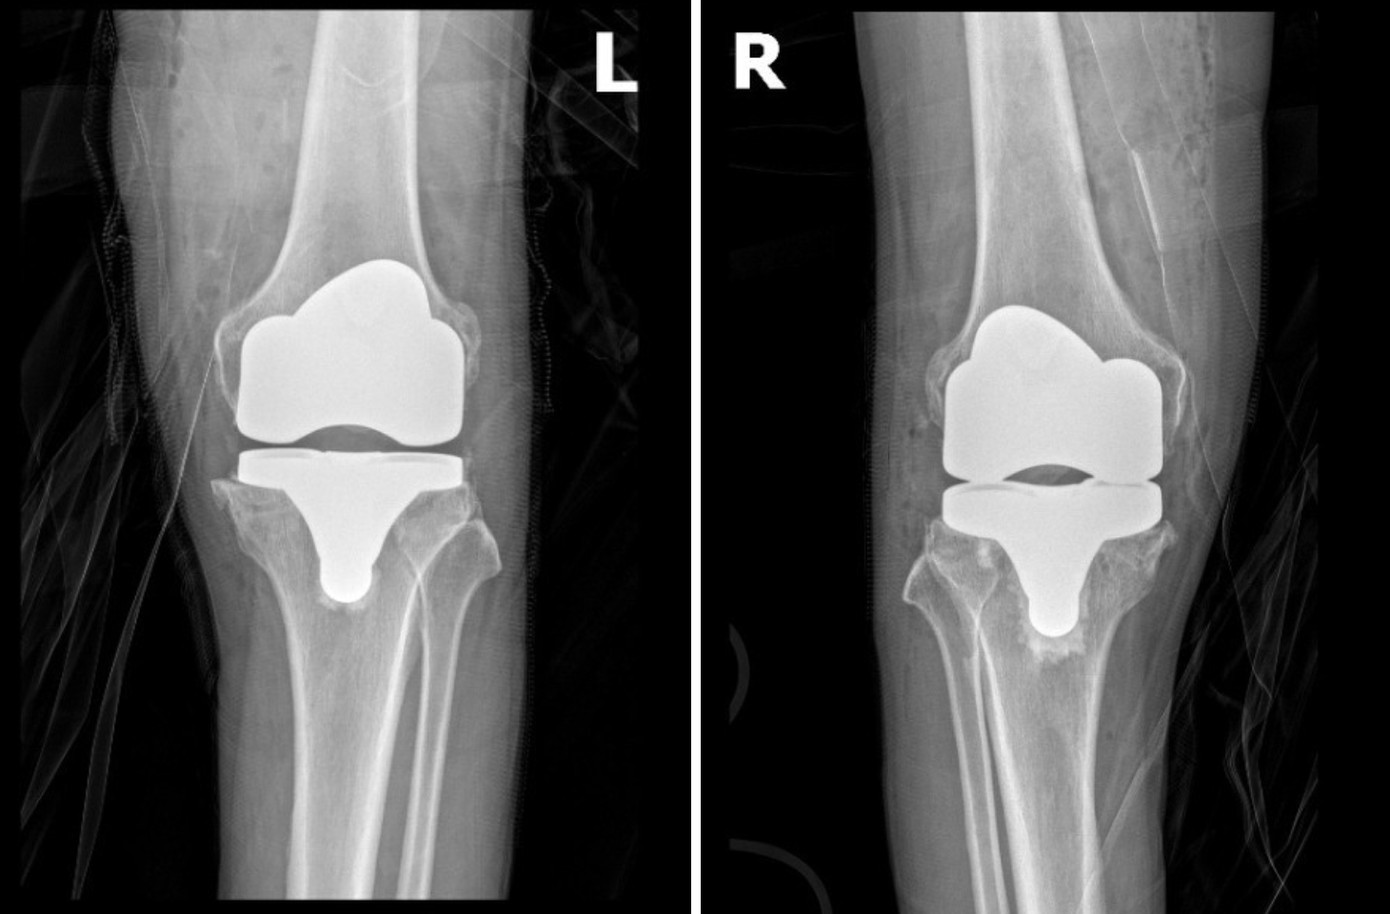

![]() |

| Phim chụp khớp gối bệnh nhân Thau sau phẫu thuật với khớp nhân tạo vừa vặn với trục chân, vận động trơn tru |

Trong gần 2 tiếng phẫu thuật, ông Thau không cần phải truyền máu và chỉ số huyết áp luôn trong trạng thái ổn định. Chỉ 1 ngày sau phẫu thuật, ông đã tỉnh táo và bắt đầu chế độ tập Phục hồi chức năng sớm, từng bước khôi phục vận động.“Tôi vui lắm, lâu lắm rồi tôi mới có cảm giác không đau chân và ngủ ngon như vậy. Cứ cái đà này thì chắc chỉ mấy tháng nữa là tôi đi bộ thể dục được cùng mấy ông bạn rồi!” - Bệnh nhân Thau mừng rỡ nói.